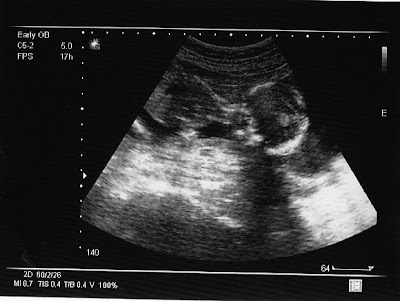

It's a... BOY!!!

Hi everyone! We just found out what we're having today! It's a boy! Here are some ultrasound pictures of him. Isn't he cute? We think so!

This is our second baby at 17 weeks and 3 days. I know...you're thinking that's the cutest thing you've ever seen! It's head is on the right (i think!) He is looking down.